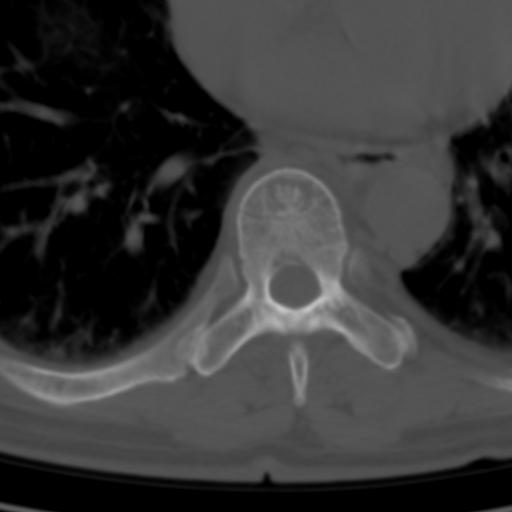

标题: CT25189:胸椎ct,请会诊!

既往食管癌,现行ct检查!

仅见椎体退行性改变

中上段食道癌,椎体轻度退变。